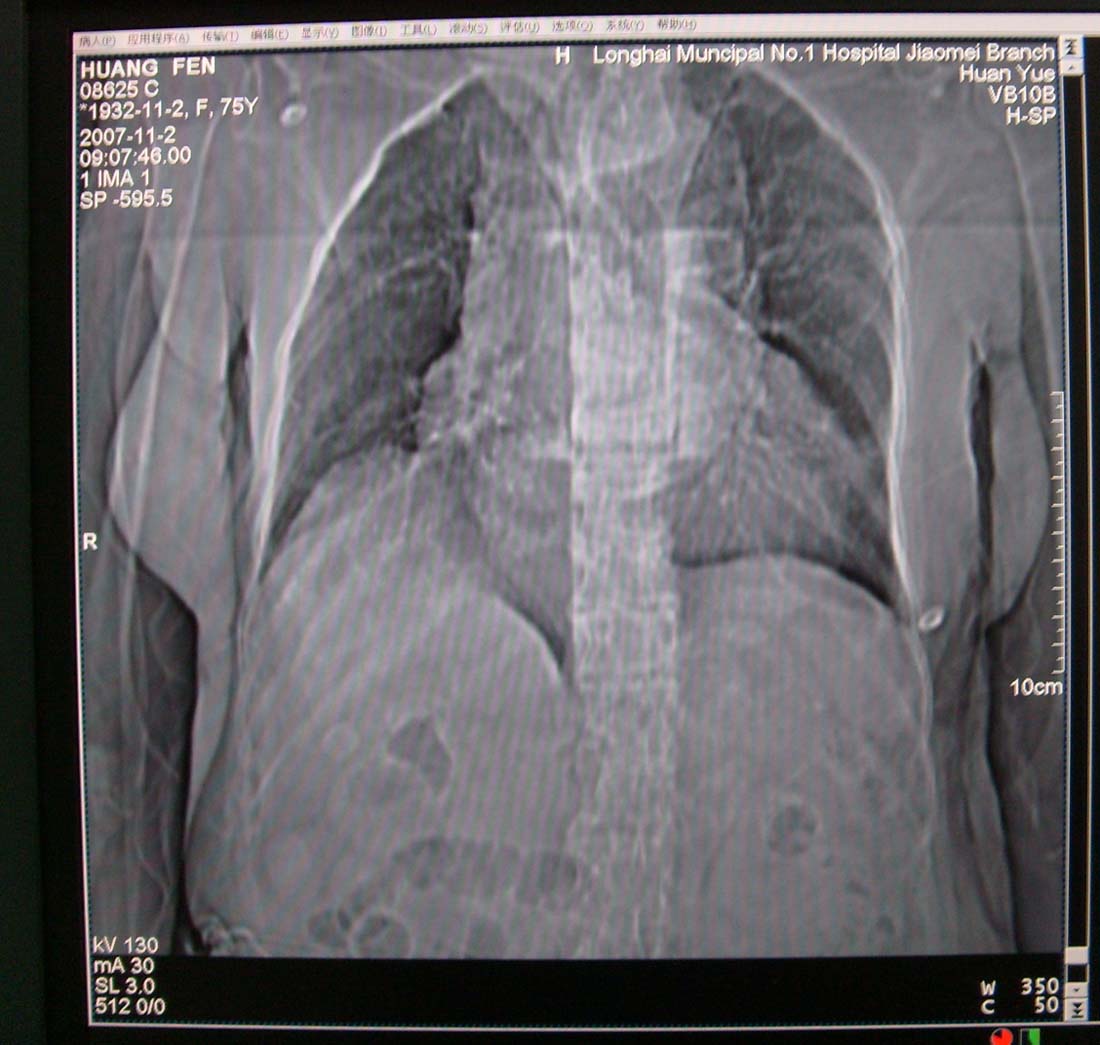

以下是引用xiaoniu在2007-11-4 12:05:00的发言:[br]这是胸主动脉迂曲延长造成的下段向右移行的影像表现,应该是:胸主动脉移行段。[br]

以下是引用nanjing在2007-11-4 12:21:00的发言:[br]降主动脉迂曲移位。